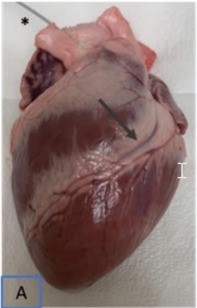

Human coronary artery with side branches. (Vardhan, 2019)

2. Vardhan, Madhurima et al. "The importance of side branches in modeling 3D hemodynamics from angiograms for patients with coronary artery disease." Scientific reports. 9,1 (2019): 8854. Distributed under Open Access license CC BY 4.0, without modification.